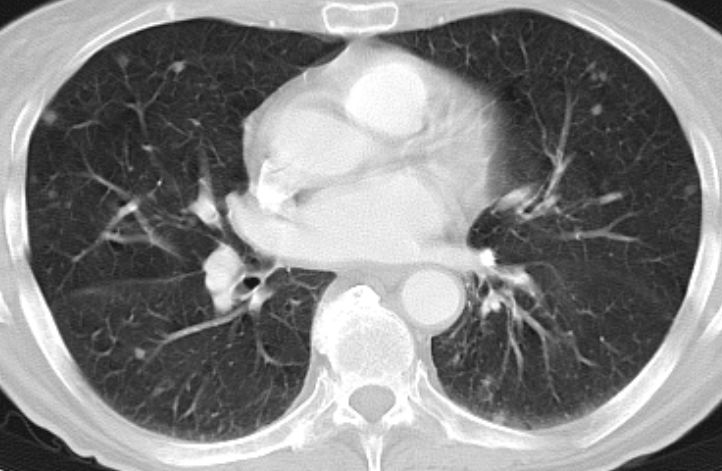

| Lunge | 75jährige Frau mit Magenantrumkarzinom. Miliare

pulmonale Aussaat.![]() |

50-jähriger Mann mit primär hepatisch und

pulmonal metastasiertem Antrumkarzinom.![]() | |